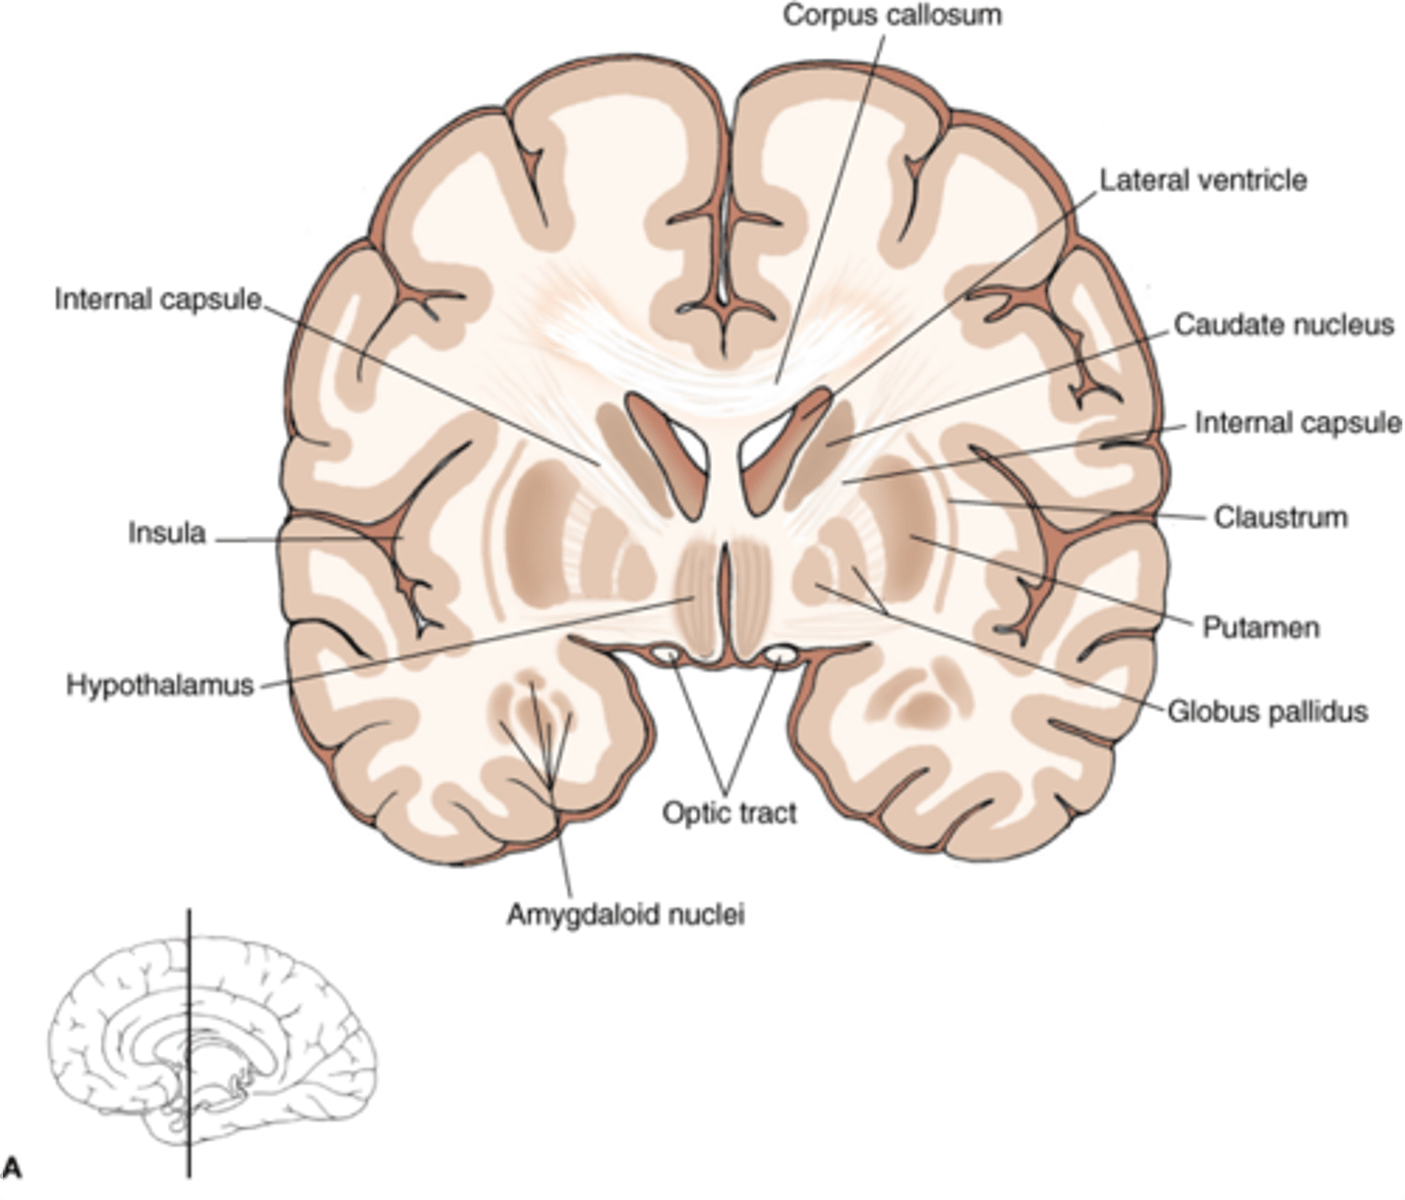

what are 3 key white matter structures found in the cerebrum?

1. corpus callosum

2. corona radiata

3. internal capsule

what cerebral white matter structure is a large bundle of nerve fibers that connects the left and right cerebral hemispheres, allowing them to communicate?

corpus callosum

what is the fan-shaped cerebral white matter sheet that is continuous ventrally with the internal capsule?

corona radiata

what cerebral white matter structure is a tract that carries sensory and motor information to and from the cerebral cortex?

internal capsule

what cerebral white matter structure is found between the basal ganglia?

internal capsule

what are the 3 regions of the internal capsule?

1. anterior limb

2. genu

3. posterior limb

what cerebral gray matter structure is a collection of subcortical nuclei primarily involved in motor control?

basal ganglia

what cerebral gray matter structure has a gate-keeping mechanism for the initiation of motor movement (choosing which actions to allow and which to inhibit)?

basal ganglia

what cerebral gray matter structure has roles in motor learning, executive functions, behaviors, and emotions?

basal ganglia

what are the 3 parts of the basal ganglia? what runs between them?

1. caudate nucleus

2. putamen

3. globus pallidus

internal capsule

what part of the basal ganglia is the C-shaped structure that is most medial?

caudate nucleus

what part of the basal ganglia is medial to the putamen?

globus pallidus

the putamen and globus pallidus of the basal ganglia are collectively called the _______________ nucleus

lentiform